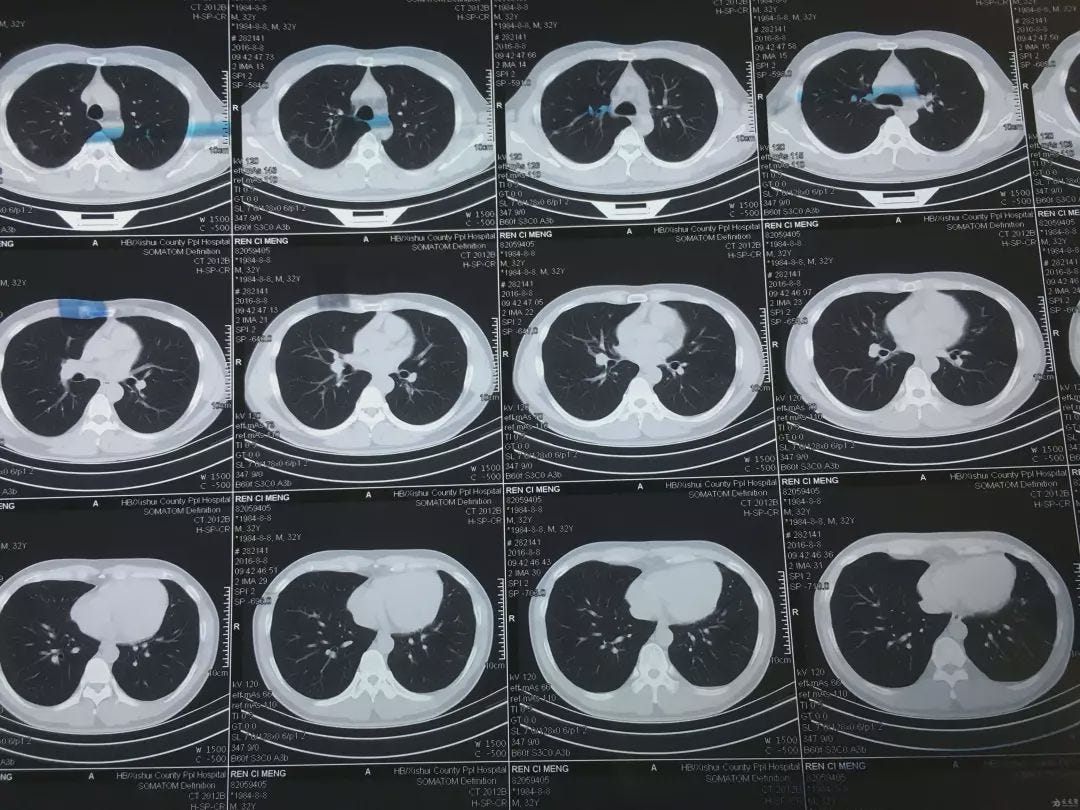

Multiple layers of CT scan images used in the annotation process.